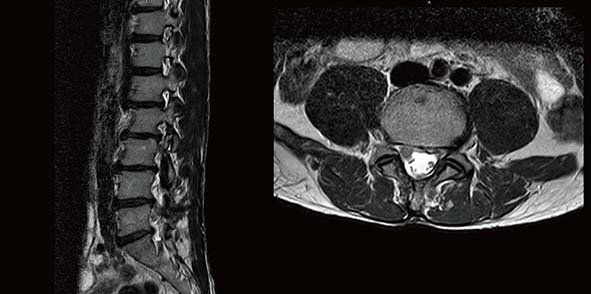

高市50歲張姓男子衝浪後突感右小腿外側及臀部疼痛,感覺像,就醫核磁共振檢查發現腰椎第四、五節椎間盤斷裂,壓迫右側第五對神經根,手術治療雖獲改善,但腳掌無法翹起,轉診七賢脊椎外科醫院經副院長蔡東翰確診肇因合併腓神經壓迫,建議施作腓神經鬆解術,局部麻醉半小時完成,後續復原快速。

蔡東翰表示,張男腰部椎間盤壓迫神經根及腓神經,造成小腿外側痛麻及翹起,可運用膝蓋肌腱反射辨識,如出現相關症狀最好求助專業醫師。圖/七賢脊椎外科醫院提供、文/高培德